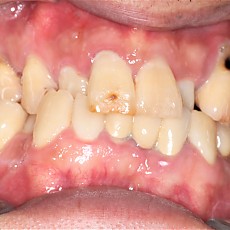

시술전후사진 6 페이지

Total 189건 6 페이지